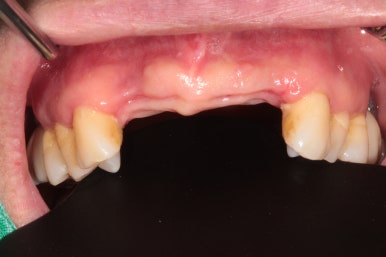

50대 여자 환자분입니다. 처음에 내원하셨을 때 정면 사진이에요.

딱 보아도 잇몸 상태가 참 좋지 않았습니다. ㅠㅠ 특히 위 앞니는 가만히 있어도 고름이 나오고 있는 상태지요..

만성치주염을 갖고 계신 환자분들은 이러한 상황을 조심하셔야 합니다.. 너무 방치되면 정말 임플란트를 심을 잇몸뼈가 하나도 남지 않을 수 있어요.... 그러다 진짜 틀니 하셔야 합니다!!...